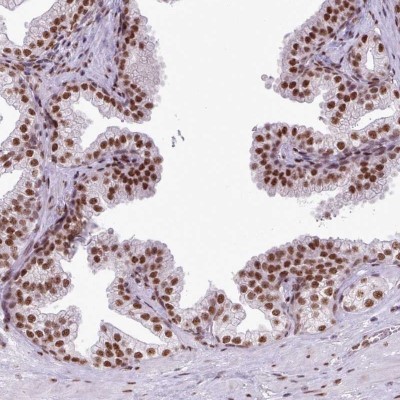

- Main image

- Experimental details

- Immunohistochemistry-Paraffin: FAM182B Antibody [NBP2-33590] - Staining of human prostate shows strong nuclear positivity in glandular cells.